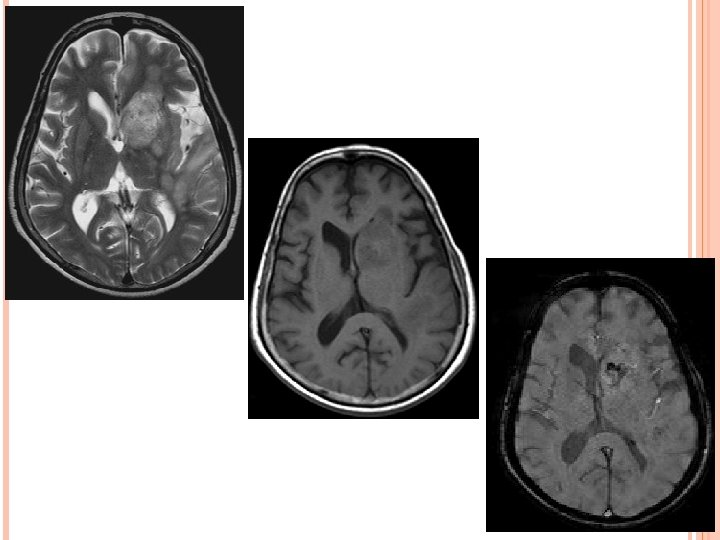

TOXOPLASMOSIS Infection by parasite T. gondii, present as altered sensorium, headache and mild hemiparesis. Multifocal involvement more common than solitary. Typically Supra-tentorial. Corticomedullary junction , Basal Ganglia, Thalamus, Intraventicular. Necrotising abscess. D/D-Lymphoma.

TOXOPLASMOSIS CT Plain CT – iso to hypodense with edema. CECT – no enhancement, minimal, ring or nodular enhancement. MRI T 1 WI – Iso to Hypointense but occasionally hyperintense due to hemorrhage which differentiate it from lymphoma. T 2 WI – Hypo- to isointense and are surrounded by high-signalintensity vasogenic edema. T 1 W+C—Ring or nodular enhancement with sometimes an eccentric mural nodule (eccentric target sign).